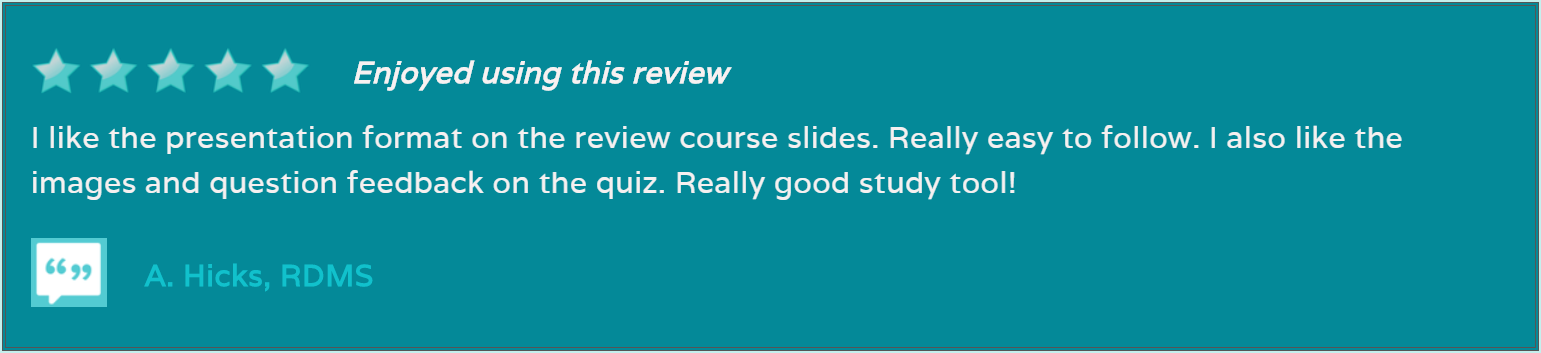

Test & Learn format to help you learn as you go

Registry Review Quiz

Our Pediatric Echo Registry Review - Test & Learn Quiz can help you prepare for your pediatric echo registry exam. No need to be intimidated. Our unlimited quiz has over 500 questions in the question bank and will help you learn as you go, testing your knowledge and teaching too! Our test responses are based on your answers and questions are designed to help you learn as you go with exam questions and answers, rotated and randomized with each 50 question quiz attempt. Become a registered pediatric or congenital cardiac sonographer. Pass your ARDMS® RDCS (PE) or CCI® RCCS echo registries. Become a registered pediatric or congenital cardiac sonographer - study with us today!

We have developed our Test & Learn Registry Review Quiz to help you learn as you go, with questions and answers that rotate with each attempt and questions with feedback based on your quiz answers. Our study resources are prepared by multi-credentialed sonographers with expertise in pediatric and congenital echocardiography, proven to help you master the content and pass your ARDMS® RDCS (PE) or CCI® RCCS registry exam, with several purchase options designed for every budget. Study with us today!